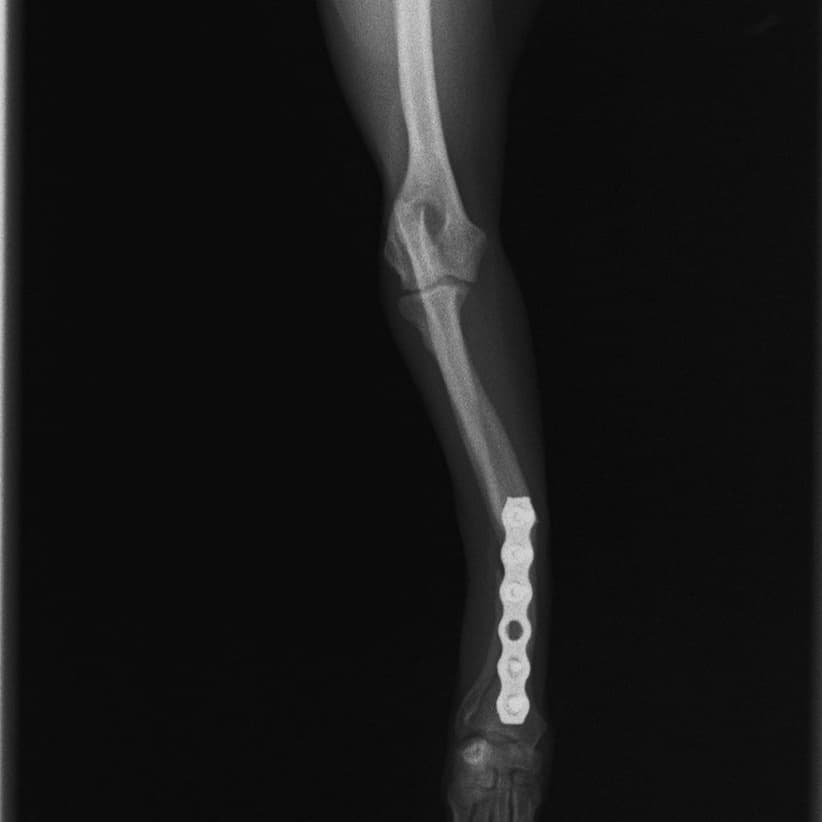

他院にて左大腿骨遠位の成長板骨折(salter-harrisⅠ型)が認められており、治療相談を目的として来院。当院にて、キルシュナーワイヤーを用いたピンニングにより骨折部位の整復を行いました。術後の経過は良好で、現在も経過観察中です。

術後レントゲン